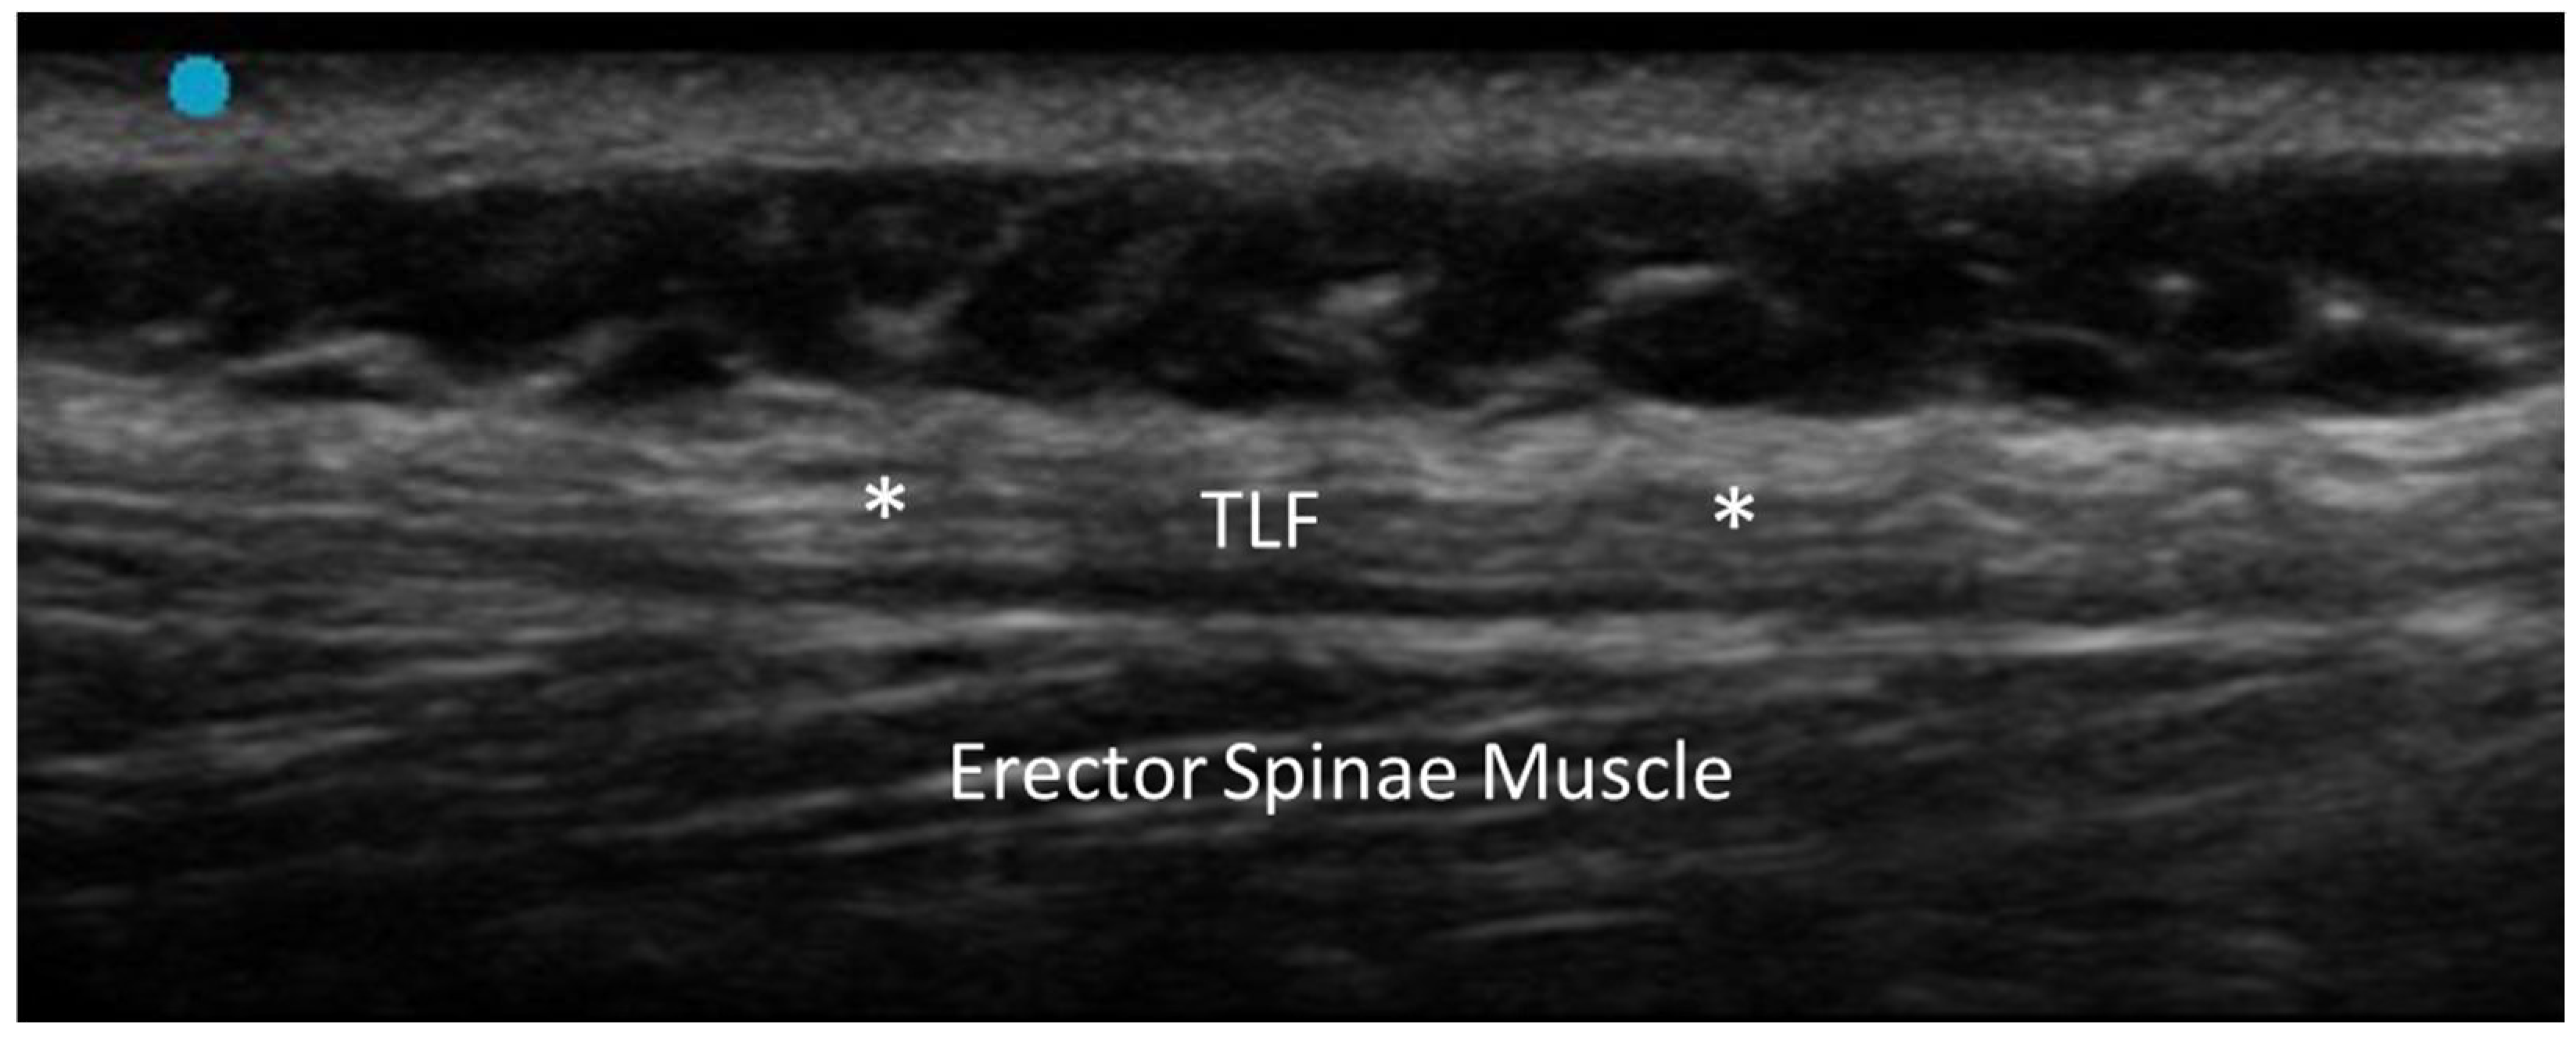

- Pirri, C.; Pirri, N.; Guidolin, D.; Macchi, V.; Porzionato, A.; De Caro, R.; Stecco, C. Ultrasound Imaging of Thoracolumbar Fascia Thickness: Chronic Non-Specific Lower Back Pain versus Healthy Subjects; A Sign of a “Frozen Back”? Diagnostics 2023, 13, 1436. [Google Scholar] [CrossRef] [PubMed] [PubMed Central]

- Griefahn, A.; Oehlmann, J.; Zalpour, C.; von Piekartz, H. Do exercises with the Foam Roller have a short-term impact on the thoracolumbar fascia?—A randomized controlled trial. J. Bodyw. Mov. Ther. 2017, 21, 186–193. [Google Scholar] [CrossRef] [PubMed]